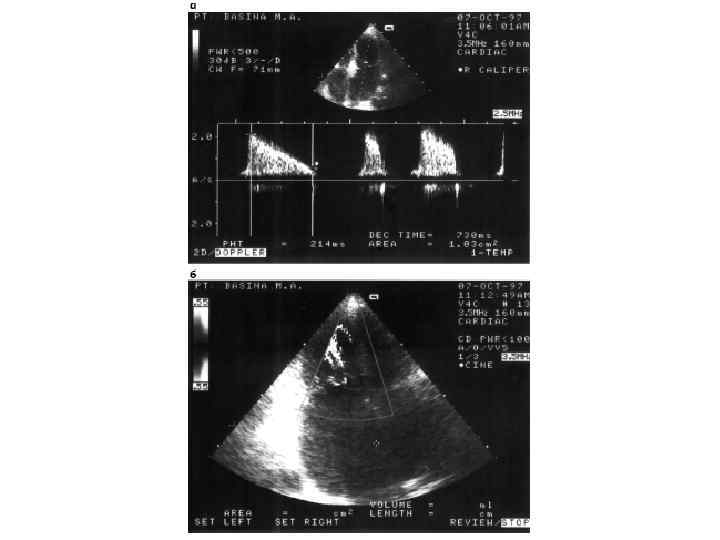

Митральный стеноз (стеноз левого атриовентрикулярного отверстия) Митральный стеноз – порок сердца, при котором суженное митральное отверстие служит препятствием для изгнания крови из левого предсердия в левый желудочек.

Механизмы компенсации 1. Повышается давление в полости левого предсердия (от 5 мм рт. ст. в норме до 20– 25 мм рт. ст. ); увеличивается разность (градиент ) давления левого предсердия — левого желудочка, что облегчает прохождение крови через суженное атриовентрикулярное отверстие. 2. Удлиняетс я систола левого предсердия; кровь в левый желудочек поступает в течение более длительного времени. 3. Гипертрофия мышцы левого предсердия — является следствием длительной перегрузки предсердия давлением. 4. Прогрессирующее уменьшение площади левого атриовентрикулярного отверстия вызывает дальнейший рост давления в левом предсердии, что приводит к ретроградному повышению давления в легочных венах и капиллярах. Повышается давление в легочной артерии, развивается пассивная, ретроградная, венозная, посткапиллярная легочная гипертензия. Давление в легочной артерии 30– 60 мм рт. ст. (в норме до 25 мм рт. ст. ). Развивается гипертензия правого желудочка. 5. Дальнейший рост давления в левом предсердии и легочных венах вследствие раздражения барорецепторов вызывает рефлекторное сужение артериол (рефлекс Китаева). Это ведет к значительному повышению давления в легочной артерии (60– 200 мм рт. ст. ), развивается активная, артериальная, прекапиллярная гипертензия. Рефлекс Китаева выполняет защитную роль, предохраняя легочные капилляры от чрезмерного повышения давления и выпотевания жидкой части крови в полости альвеол.